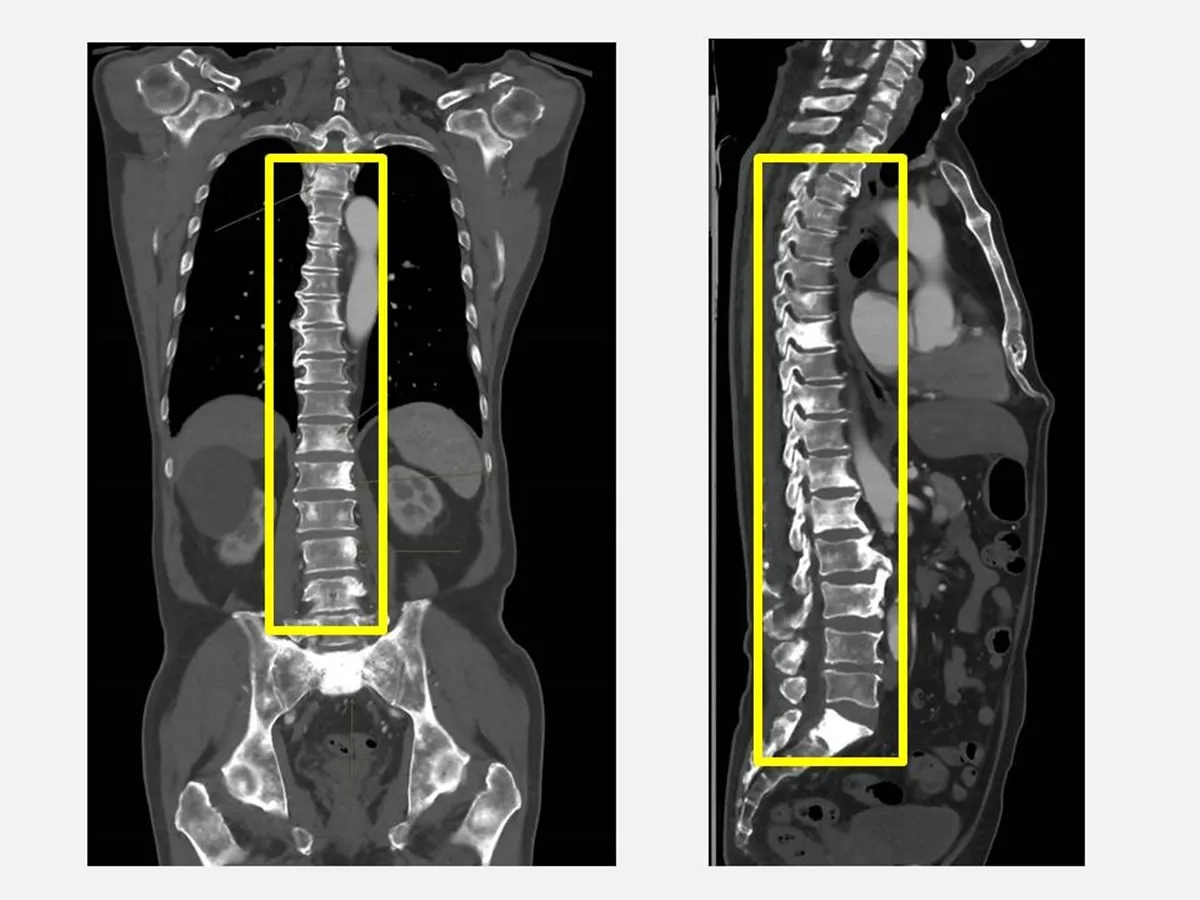

余先生在健檢中發現攝護腺特異抗原PSA與鹼性磷酸酶ALK-P指數明顯異常,健康管理中心醫師敏銳覺察可能是攝護腺癌轉移,隨即安排影像檢查並轉介至泌尿科劉緯陽主任門診。

經過進一步檢查,確診為攝護腺癌合併瀰漫性骨轉移,所幸透過跨科合作及早確認,目前已展開治療並穩定控制。